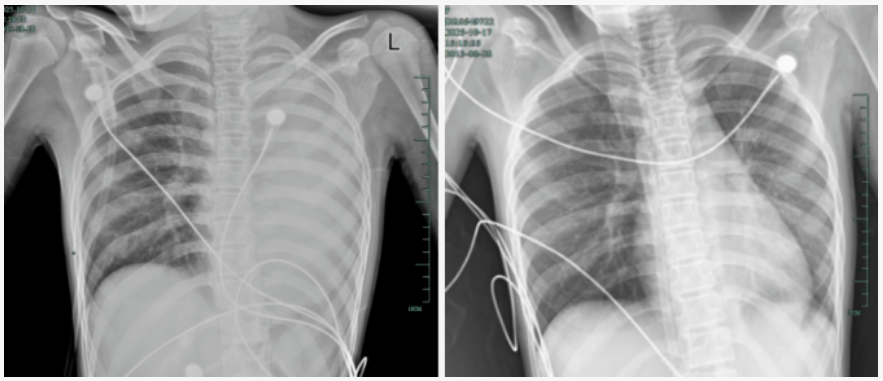

治療前后影像對比,左肺從“白肺”到正常狀態(tài)。

據(jù)介紹,笑笑一開始只是輕微咳嗽,發(fā)熱到38℃,檢查提示肺炎、肺不張,轉(zhuǎn)診到浙大四院兒科時,病情已經(jīng)急劇惡化,出現(xiàn)呼吸急促、胸悶胸痛,體溫38.5℃,只能靠5L/min的面罩吸氧維持血氧,胸片顯示左肺已完全呈 “白肺” 改變,肺部炎癥進(jìn)展迅猛。